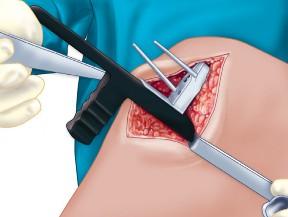

2. الوضع الجراحي والتعرض

- الوضع: يُوضع المريض في وضع الاستلقاء (Supine positioning) مع وضع كيس رمل أسفل الركبة أو حامل للساق يسمح بثني وفرد الركبة. يجب أن يكون الوضع مماثلاً لوضع جراحة TKA، مع استعداد لتحويل الإجراء إلى TKA إذا لزم الأمر.

- العاصبة (Tourniquet): تُستخدم عاصبة وتُوضع في أعلى الفخذ لتقليل النزيف.

-

الشق الجراحي:

يُستخدم شق طولي في الجانب الإنسي (الداخلي) من الركبة. يجب أن يكون الشق كبيرًا بما يكفي لتوفير رؤية جيدة للمفصل الرضفي الفخذي وإمكانية التحويل إلى TKA.

- فتح المفصل (Arthrotomy): يكون الفتح خطيًا وموازياً لألياف الوتر الرضفي، ويمتد إلى عظم الظنبوب وإلى الجزء السفلي من الرضفة.

- تحرير الأنسجة الرخوة: يتم قطع الغضروف الهلالي لتحرير الأنسجة الرخوة من عظم الظنبوب، ويتم تطوير سديلة تحت السمحاق في نمط دائري حول الظنبوب. يُمدد هذا التحرير خلفيًا لضمان توازن الأربطة.

-

تصحيح التشوه:

الهدف هو تحقيق تصحيح طفيف للتشوه، مع وجود رخاوة كاذبة طفيفة عند تطبيق ضغط تفحجي في نهاية الإجراء. يجب تجنب التصحيح المفرط.